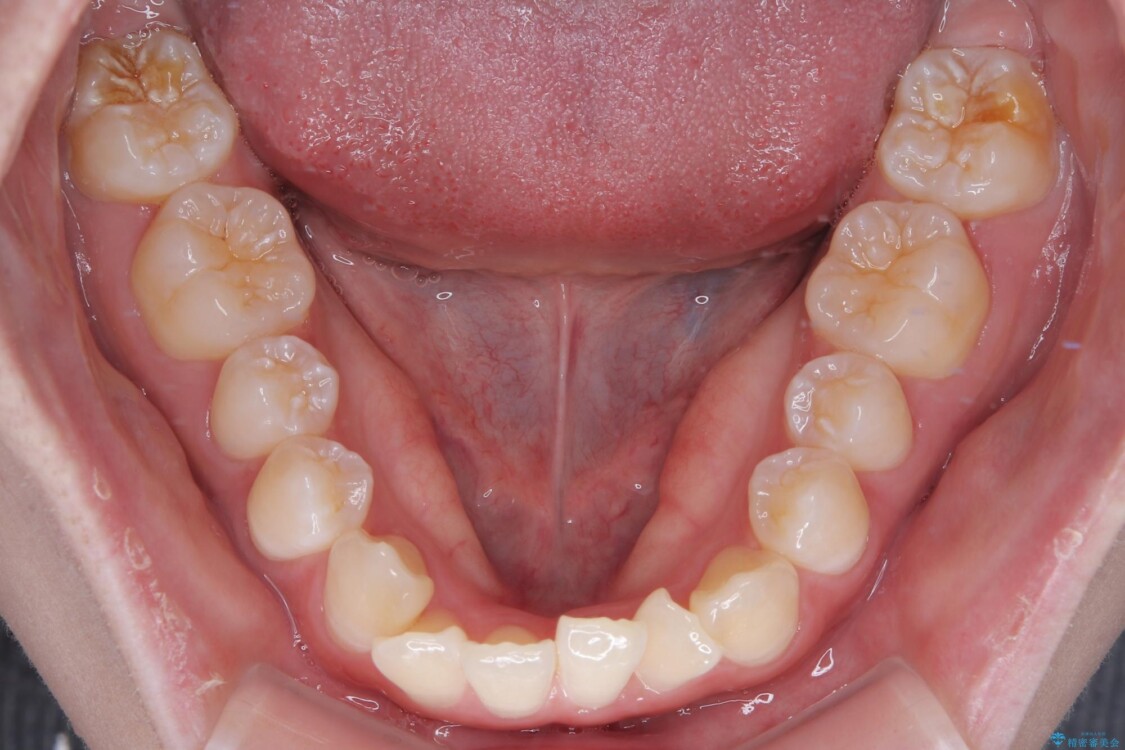

治療前

• 【モニター】前歯のデコボコをスッキリ解消!目立ちにくいワイヤー矯正でスピーディに治療完了 治療前画像

「前歯のデコボコ(叢生)をきれいに整えたい」とのことでご来院されました。